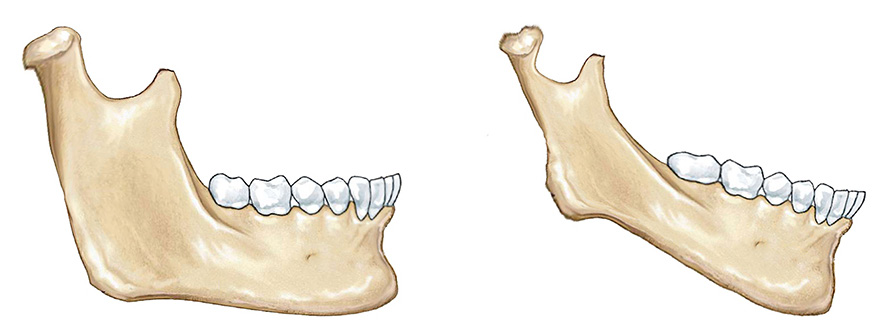

因为我们观察很多孩子当她换完牙的时候,比如说可能到了十二三、四岁之后,这个时候孩子往往会出现骨骼的问题,比如嘴凸或下巴小,或者是下巴大,或者脸歪大小脸。

但是你们知道吗?这种骨骼的问题,实际上在最初它都是牙齿拥挤不齐所导致的,而牙齿拥挤不齐,它会带来下颌骨位置的移动,会带来肌肉的变化、牙齿咬合的变化、牙齿的位置的变化,也就是说牙齿的因素与肌肉、骨骼,这几个因素就相互缠绕在一起了。

因此我们必须在孩子换牙期间,给孩子进行人为的干预和矫正。我们就可以帮助牙齿引导到正确的位置,从而能改变骨骼的位置。

因此早期矫正的意义就是我们不仅能矫正牙齿,我们更可以的去改变骨骼的位置,从而改变肌肉的形态和习惯,从而确定一个正常的生长的轨道,而这个正常生长的轨道,就是我们想让孩子达到的一个理想的面型。

那骨骼位置稳定了牙齿位置,牙齿萌出轨道生长好了,肌肉自然也就对称了,这样的话孩子就会长得会更好看一些,因此,站在这个角度来讲,牙齿矫正一定是越早做越好。